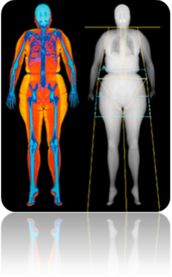

- Última generación de Densitometría con energía dual.

- Evalúa el riesgo de fracturas y futuras enfermedades óseas.